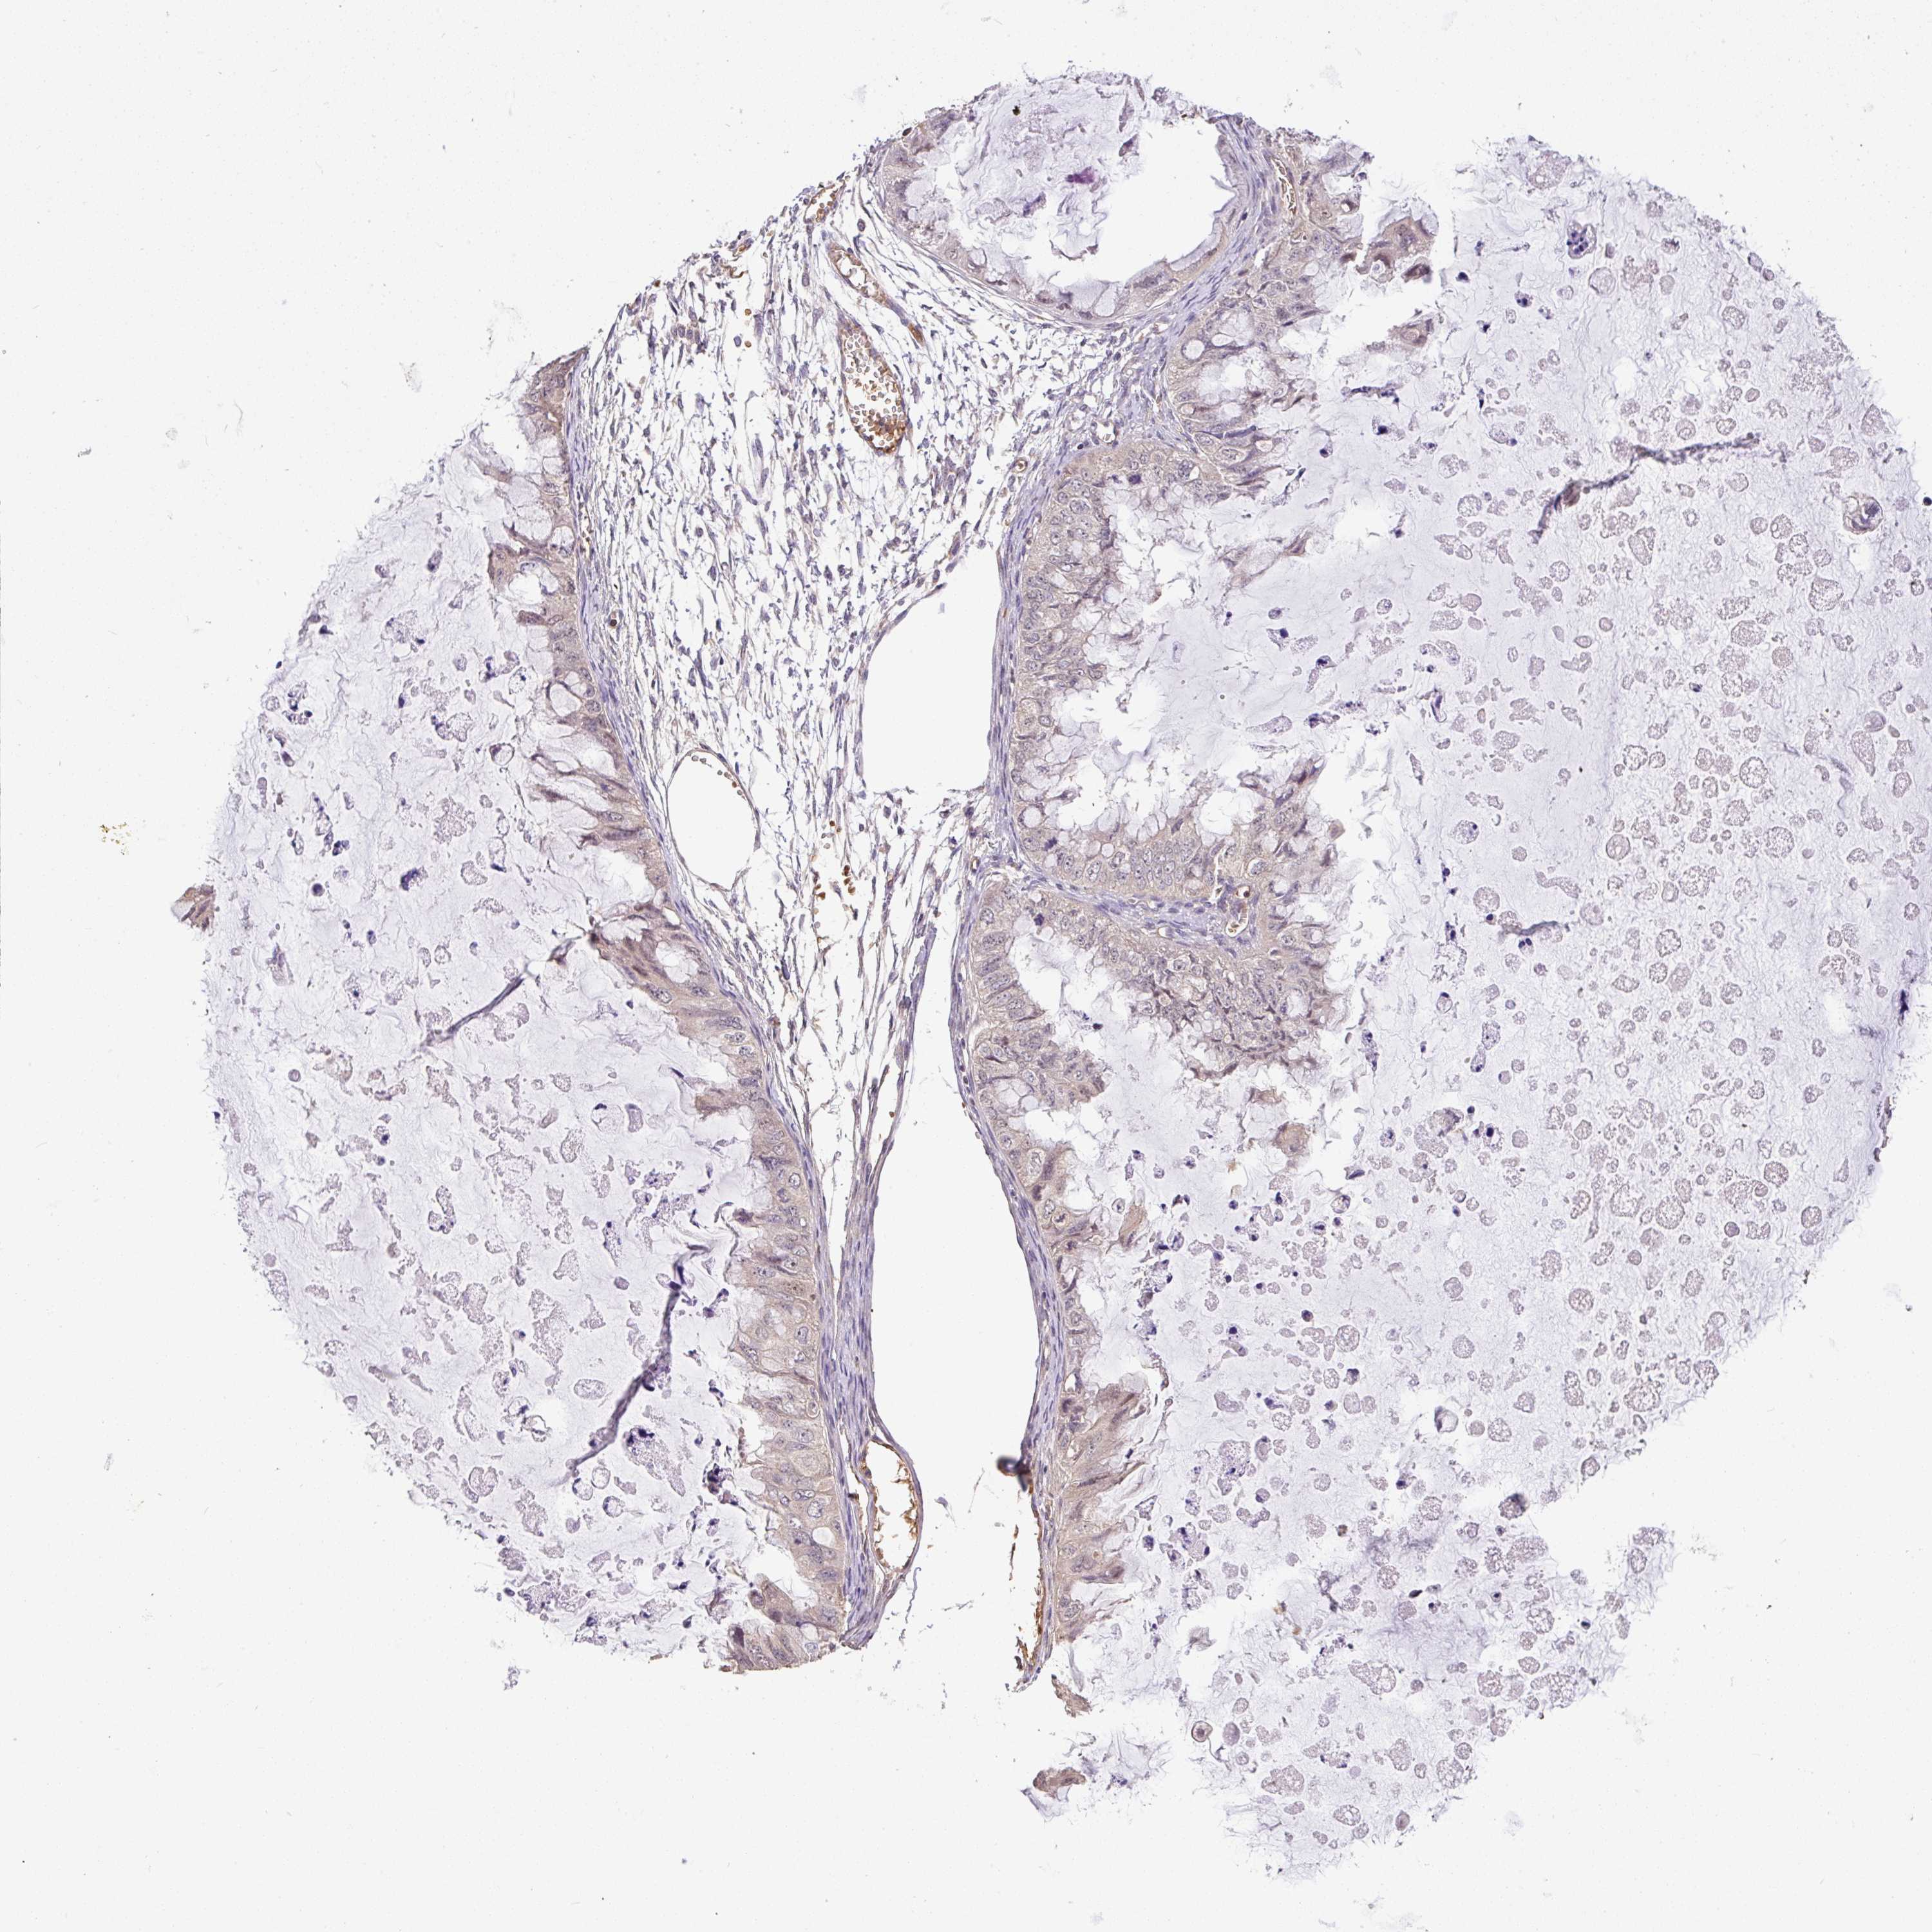

OVARIAN CANCER - Protein expressioni

A mouse-over function shows sample information and annotation data. Click on an image to view it in a full screen mode. Samples can be filtered based on level of antibody staining by selecting one or several of the following categories: high, medium, low and not detected. The assay and annotation is described here.

Note that samples used for immunohistochemistry by the Human Protein Atlas do not correspond to samples in the TCGA dataset.

Antibody stainingi

Antibody staining in the annotated cell types in the current human tissue is reported as not detected, low, medium, or high, based on conventional immunohistochemistry profiling in selected tissues. This score is based on the combination of the staining intensity and fraction of stained cells.

Each image is clickable and will lead to virtual microscopy that enables deeper exploration of all samples and also displays staining intensity scores, fraction scores and subcellular localization as well as patient and tissue information for each sample.

Antibody HPA056632

Staining

High

Medium

Low

Not detected

Intensity

Strong

Moderate

Weak

Negative

Quantity

>75%

75%-25%

<25%

None

Location

Nuclear

Cytoplasmic/membranous

Cytoplasmic/membranous,nuclear

Cystadenocarcinoma, serous, NOS

Cystadenocarcinoma, mucinous, NOS

Carcinoma, endometroid